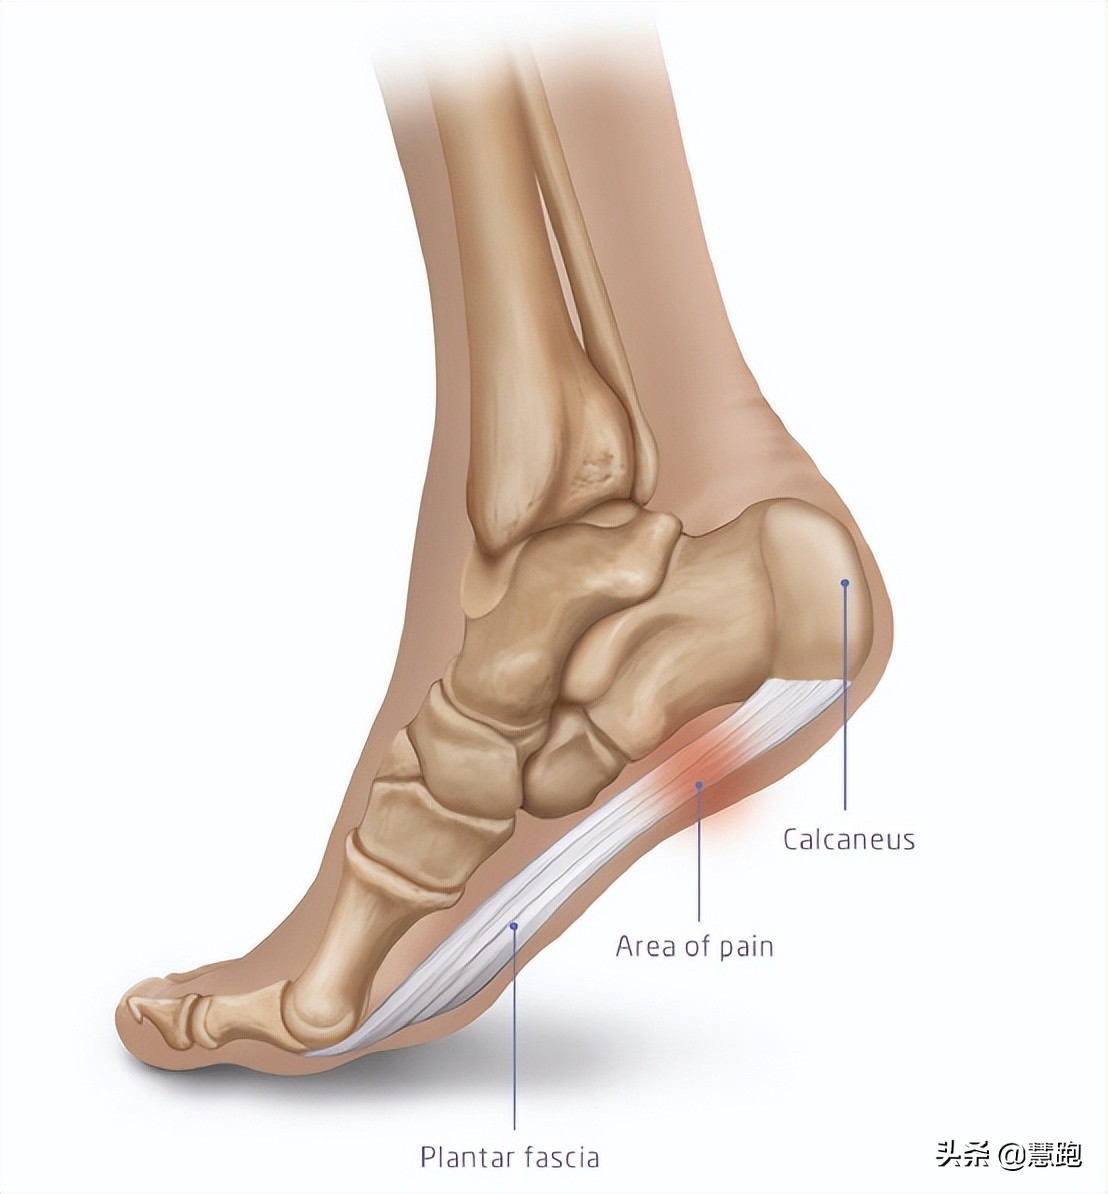

跑者十分常见的足底痛、跟腱痛,就属于比较典型的经久不愈,反复困扰跑者的顽疾,这两个部位的伤痛的名称分别是足底筋膜炎、跟腱炎。

腱病是一大类疾病的总称,发生在某个部位,就以这个部位命名,比如髌腱炎、跟腱炎、冈上肌肌腱炎、肱骨外上髁炎等等,这类病主要表现为肌腱-骨骼连接处由于受到反复、过度力学负荷,引发疼痛、压痛甚至断裂。

足底筋膜炎的典型表现

患有足底筋膜炎当然会感觉足底疼痛,疼痛的具体特点包括以下几方面:

● 最典型症状:早晨醒后下床,脚落地时,足跟部疼痛最为明显,走动一会儿后疼痛会有所缓解;

● 典型症状:休息一段时间比如看电影、久坐工作后,或者足部在不负重一段时间后,站起行走的前几步出现隐隐作痛;

● 疼痛的具体位置实在在足跟靠内侧处,这里恰恰是足底筋膜从足跟发出的起点处,偶尔也有患者会反映疼痛在足底中部;

● 患者自己感觉在充分活动后如行走或跑步后,足跟部疼痛减轻,但是在长距离跑步后程,可能再次出现疼痛甚至被迫停下脚步,还有患者反映晚间足跟部疼痛会加重;

足跟特定部位按压疼痛和晨起下床足跟痛,是判断足底筋膜炎的重要依据。

此外,跑者可以通过一个被称为“卷扬机试验”的测试来进行自我诊断。采用坐位,握住大脚趾,将大脚趾用力背伸,如果诱发疼痛,则提示是足底筋膜炎。

有跑者到医院检查,拍片后显示有跟骨骨刺(专业术语称为跟骨骨赘),大惊失色,会认为足底长出骨刺自然戳着疼。其实,骨刺不是导致疼痛的主要原因,骨刺刺激了足底筋膜才是产生疼痛的主要原因,足底筋膜炎治好了,自然疼痛也就消失了,所以对于跟骨骨刺不必过度担心。